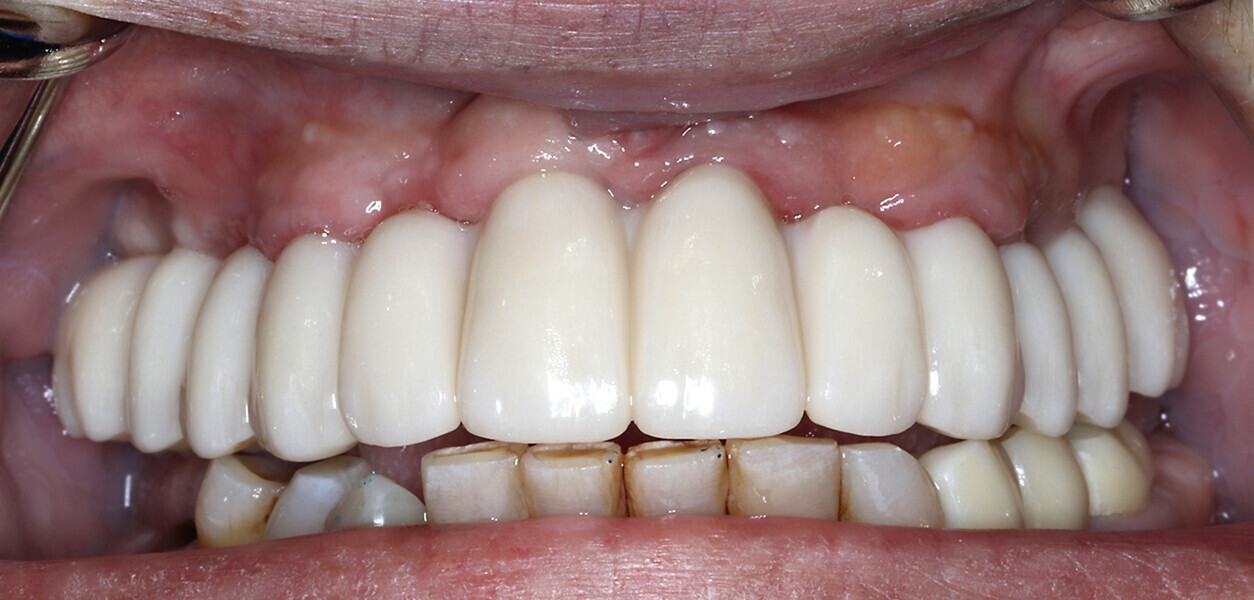

The following case exhibits the features and benefits of utilising Grammetry in combination with innovative screw technology. The 63-year-old male patient with a non-contributory medical history presented with failing dentition in both arches. Diagnostic records were collected, including full-mouth digital radiographs (RVG 6200, Carestream Dental; Fig. 11a), intra-oral scans (Medit i700 wireless; Figs. 11b & c), a large field of view CBCT scan (Carestream 9600; Fig. 11d), and intra-oral and extra-oral photographs (Fig. 11e). The mandible contained an impacted canine as well as several mobile and painful teeth. The maxilla was in a similar condition, having deteriorating, painfully mobile teeth, as well as extensive caries. While the bone loss was significant in the mandible, the vertical dimension of occlusion (VDO) allowed for both arches to be treated with an FP-1 prosthesis.

Fig. 11e: Pre-op photograph showing a reverse curve of the mandibular teeth and poor aesthetics.

Fig. 16b: Retracted intra-oral view.

Fig. 17b: Retracted intra-oral view.

The data collected was sent through a scanning software portal (Medit Scan for Clinics) to the dental laboratory with requested changes for correction of the desired smile design. Utilising advanced planning features in the design software (exocad), the midline and tooth size changes were corrected. 3D-printed maxillary and mandibular PMMA restorations were used for try-in using the direct-to-MUA screws (Vortex LA VIS; Fig. 16a). Fit, phonetics, aesthetics and occlusion were evaluated and confirmed using digital articulation (OccluSense; Fig. 16b). The patient was extremely satisfied with the printed try-ins. Since no adjustments were required, the patient was allowed to leave with the printed try-ins as new provisional restorations made from extra-strong resin. The new provisional restorations were worn for ten days to confirm form and function. The final shade was chosen, and metal-free monolithic zirconia restorations were then fabricated by the laboratory.

The final restorations were passively and accurately seated ten days later uneventfully using Vortex LA VIS screws. Confirmation records were taken with photographs, radiographs and digital articulation to recheck fit, function, phonetics and occlusion (Fig. 17a). The patient was extremely satisfied with his final restorations, describing the process as life-changing and surprisingly fast in comparison with what he had heard about full-mouth implant therapy. He was especially pleased with the speed at which the final process was able to be completed (Figs. 17b & c).